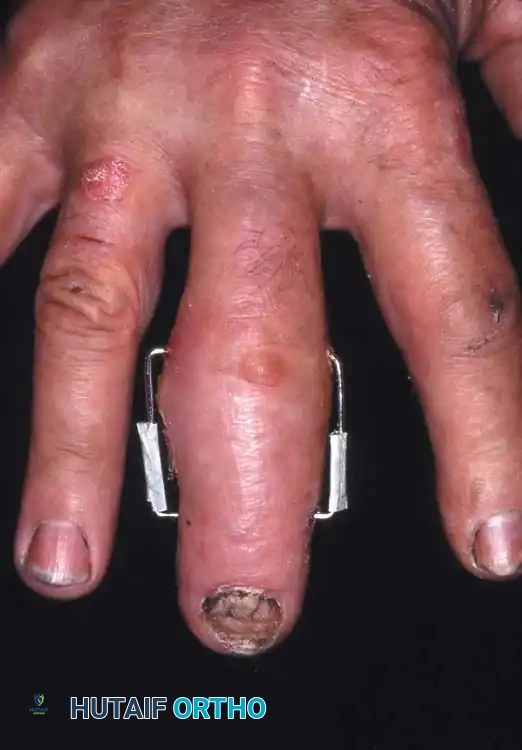

Fracture-Dislocations of the Proximal Interphalangeal (PIP) Joint

Fracture-dislocations at the PIP joint typically result in an unstable dorsal displacement of the middle phalanx. This is caused by the disruption of the volar plate's attachment to the volar lip of the middle phalanx, often accompanied by impaction of the articular surface.

Treatment is strictly dictated by the percentage of articular surface involved and the degree of comminution.